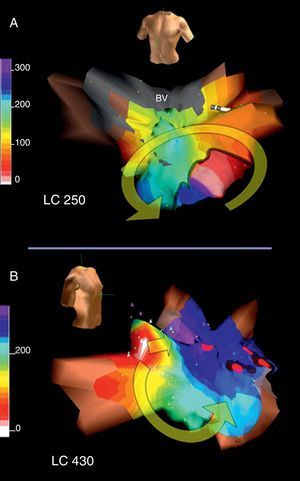

Taquicardia macrorreentrante auricular izquierdaLa estructura anatómica de la AI no contiene los grandes obstáculos de la AD, y quizá por eso las TAMR de la AI han sido poco frecuentes. En pacientes sin antecedentes de cirugía la TAMR de AI se produce en presencia de amplias áreas inexcitables de bajo voltaje y áreas de bloqueo de conducción que forman el núcleo central del circuito, ya sea por sí mismas, ya sea por su anexión a algún obstáculo anatómico (orificios de las venas pulmonares u orejuela) (Figura 12, Figura 13)17, 26, 27. La TAMR de AI se asocia a cardiopatías orgánicas (miocardiopatías, valvulopatías) y a patrones de grave trastorno de conducción interauricular (bloqueo del haz de Bachmann)28. Un sustrato frecuente de la TAMR de AI son las atriotomías quirúrgicas de cirugía valvular mitral29 o de cirugía de fibrilación auricular30. En los últimos años, el gran auge de la ablación de la fibrilación auricular, con destrucción de amplias zonas de miocardio auricular, ha dado pie a una alta incidencia de TAMR de la AI en estos pacientes31, 32, 33, que lleva a la necesidad de nuevos procedimientos de ablación en un buen número de ellos.

Figura 12. A: cartografía electroanatómica (Navx®) en visión anterior, de un circuito de taquicardia auricular macrorreentrante en torno al anillo mitral en paciente sin antecedentes quirúrgicos; obsérvese la amplia zona inexcitable de bajo voltaje (en gris) en la aurícula izquierda posterosuperior. B: cartografía en visión oblicua anterior derecha de una taquicardia auricular focal muy lenta (ciclo, 430 ms) inducible tras la interrupción de la taquicardia auricular macrorreentrante con aplicaciones de radiofrecuencia entre la zona de bajo voltaje y el anillo mitral (puntos rojos); esta taquicardia auricular focal se origina en la vena pulmonar superior derecha (área blanca); como en el caso de la figura 6, una línea de bloqueo obliga al giro del frente de activación que termina al otro lado de esta zona de bloqueo (azul-violeta). BV: bajo voltaje; LC: longitud del ciclo.